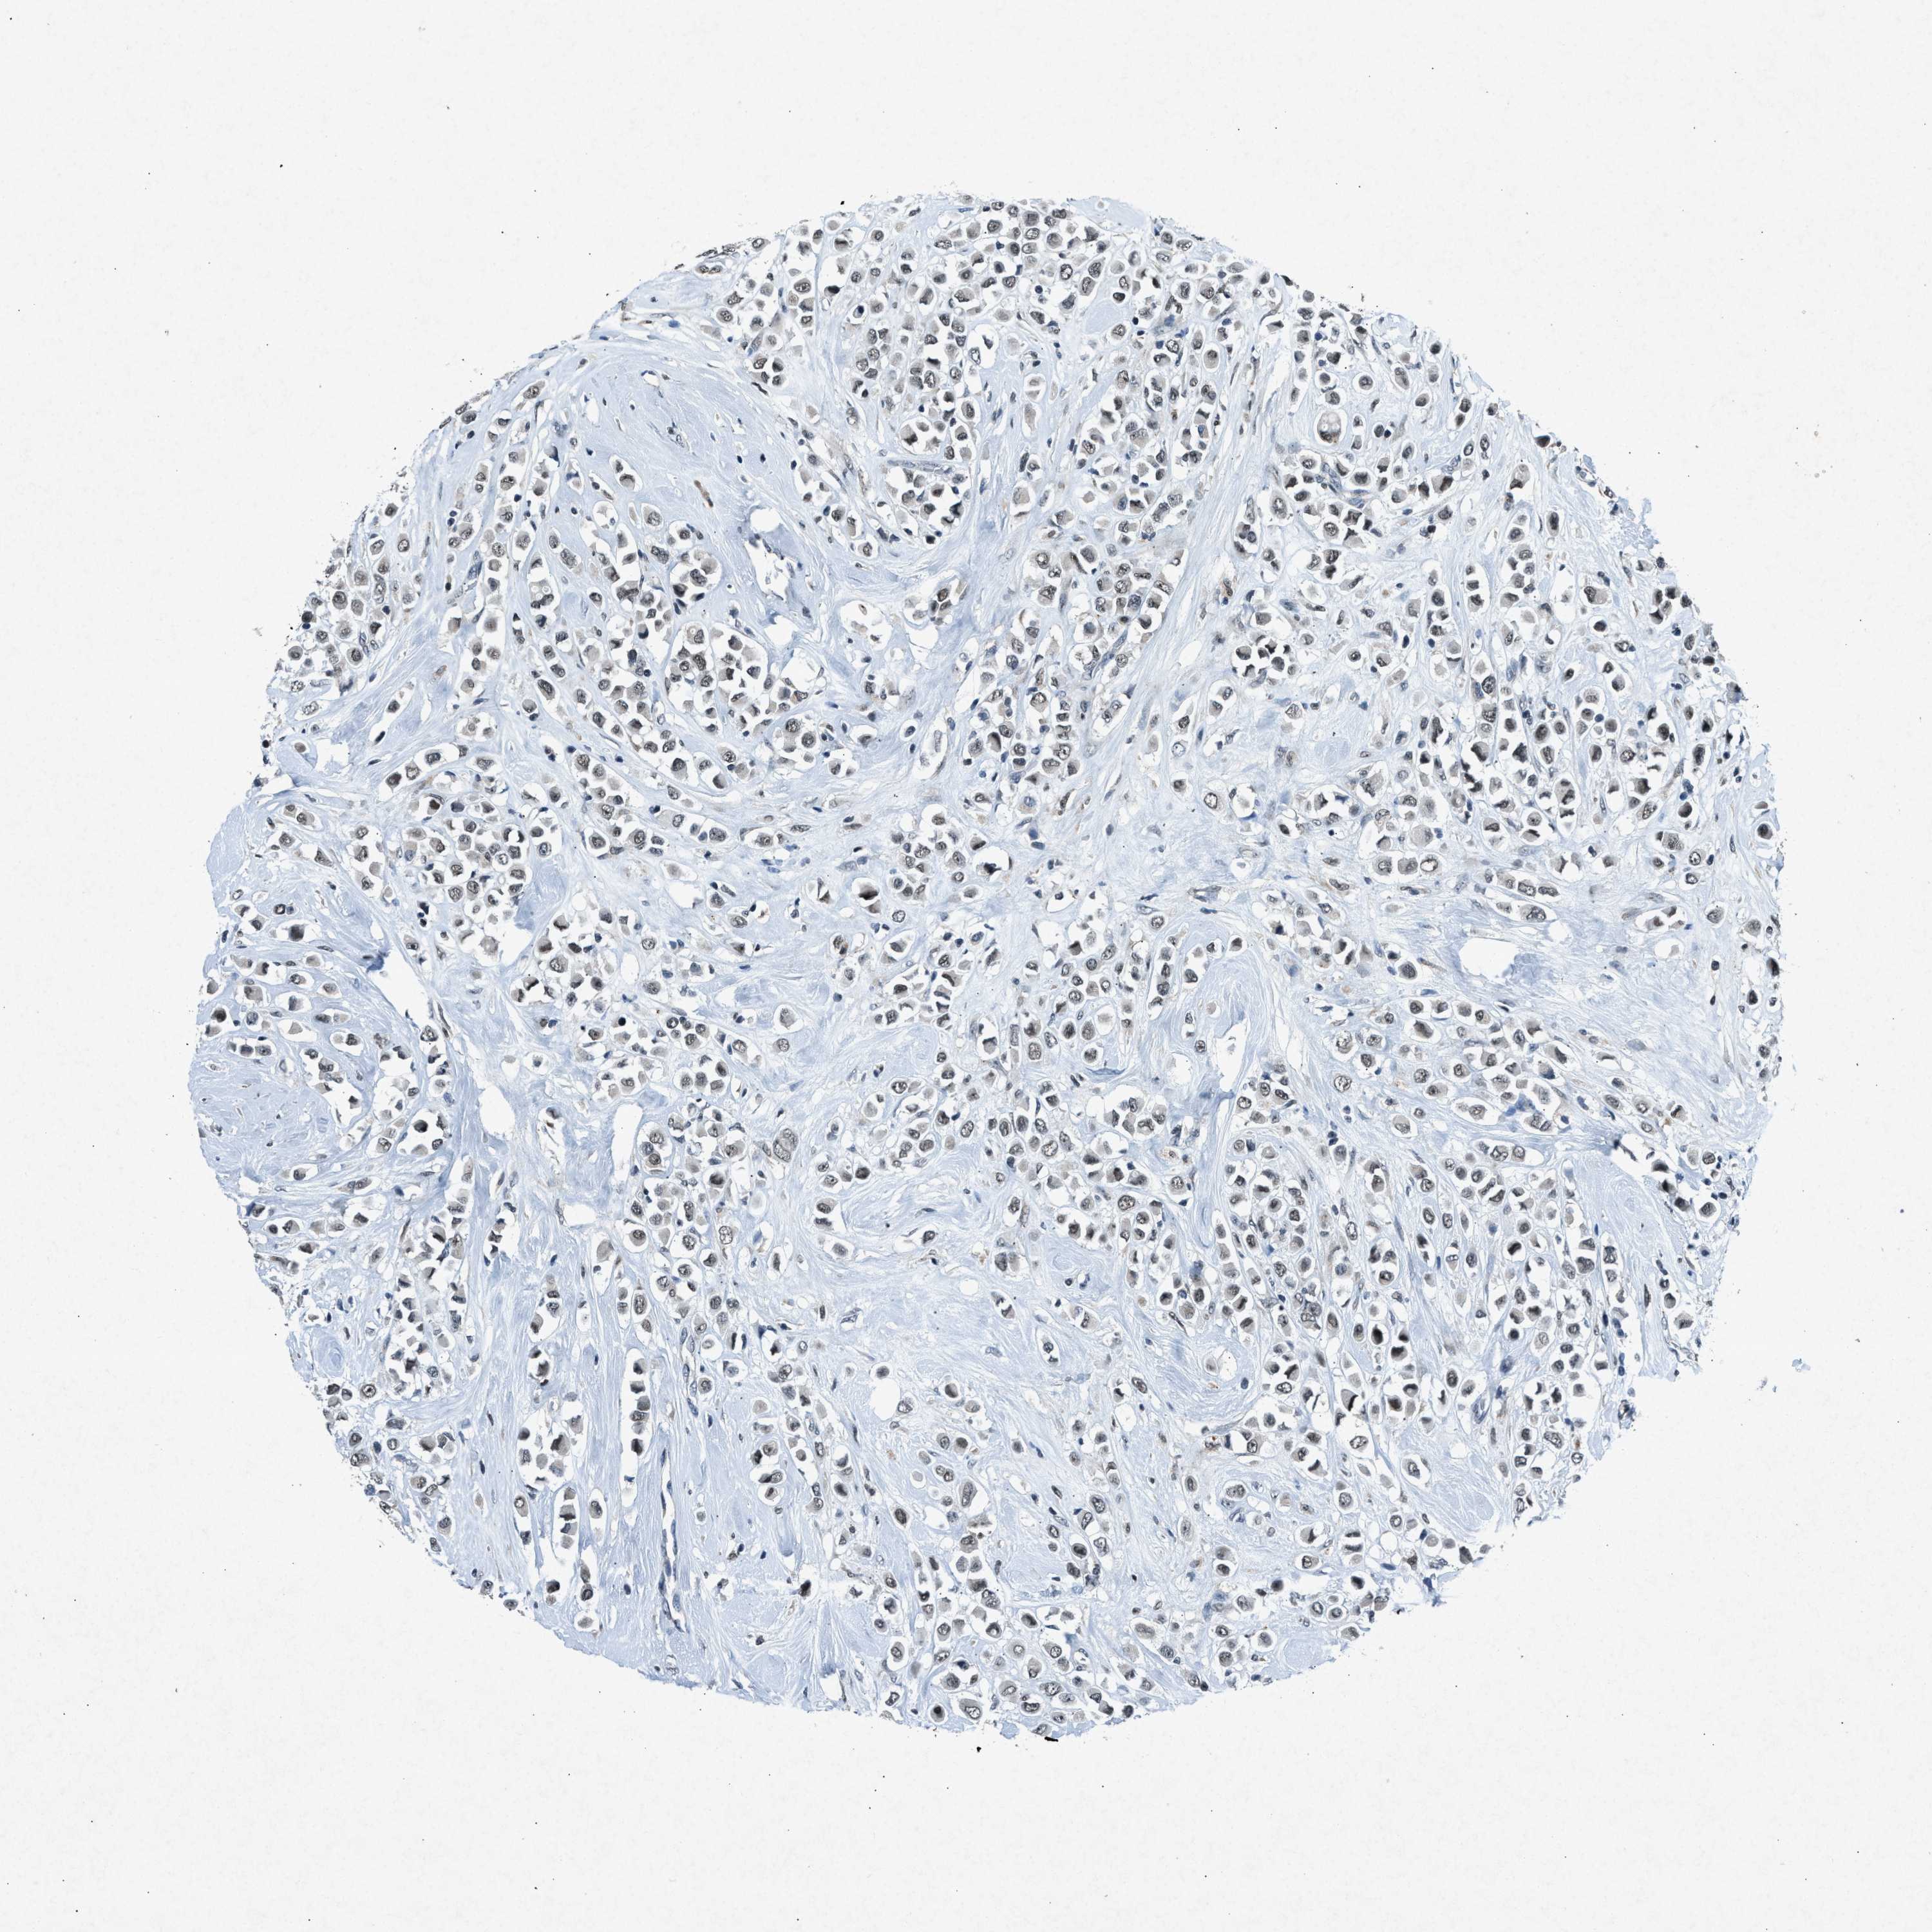

CANCER BREAST CANCER Show tissue menu

BRCA TCGA BRCA VALIDATION PROTEIN EXPRESSION